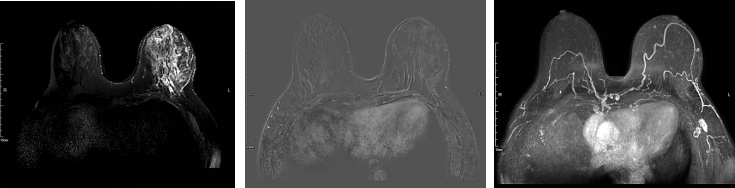

新辅助治疗:TCbHP方案6个周期。具体方案:白蛋白紫杉醇260mg/m2d1+卡铂AUC6 d1+曲妥珠单抗(汉曲优)6mg/kg(首剂8mg/kg)d1+帕妥珠单抗420mg(首剂840mg)d1,均q3w。每2个周期结合临床体检、彩超和乳腺增强MRI进行疗效评估。

▌治疗后评价

图7.新辅助治疗2周期后的乳腺增强MRI评估

图8.新辅助治疗6周期后的乳腺增强MRI评估

患者自第3周期新辅助治疗起,正处于3~6月间上海新冠疫情封控时期,对影像学评估造成了较大的影响。根据ESMO新冠期间乳腺癌诊治临床处理优先原则,对于HER2+乳腺癌的新辅助/辅助治疗作为优先实施治疗,而对于新辅助治疗临床缓解的患者的影像学评估可以适当延后。因此,对于该患者4个周期后的影像学评估没有实施。